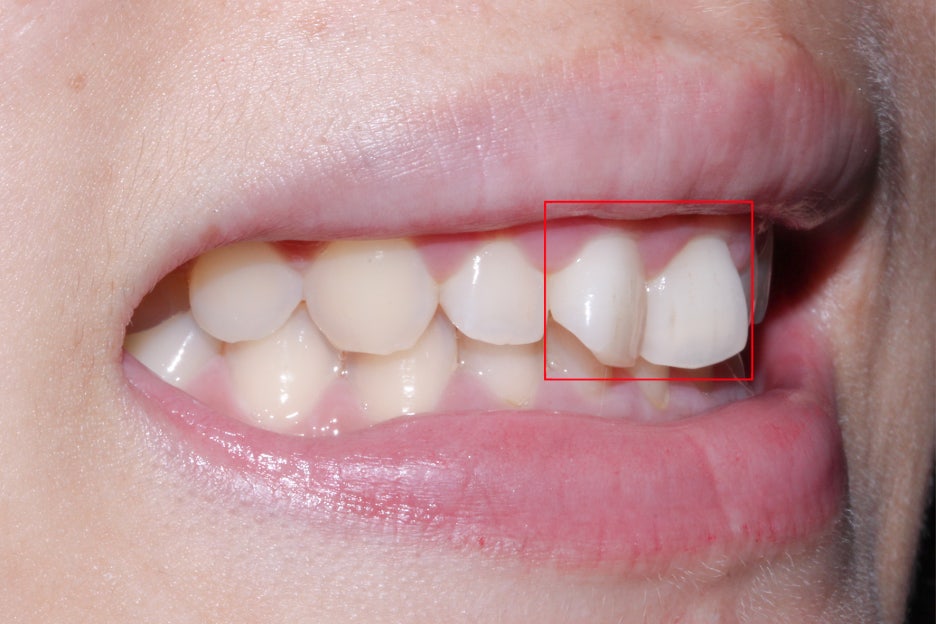

세라믹교정 전 전치부의 모습입니다.

살짝 미소를 지으면 드러나는 스마일라인에서

상악 중절치의 치축이 틀어진 모습을 확인할 수 있는데요,

정상적인 치아의 경우 중절치의 치축은

수직으로 배열되어 있어야 하지만 위의 Case에서는

중절치 2개가 나비치아 증상을 보이며 삐뚤어진 모습입니다.

문제가 있는 상악 중절치를 자세히 보면

위처럼 치아가 마주보듯이 꺾여있는 것을 확인할 수 있습니다.

이러한 회전치 증상으로 인해 전치부의 심미성이 떨어져 보이는데요,

세라믹교정 전 구내사진을 확인해보면

중절치의 회전 뿐만 아니라 양쪽의

측절치도 약간 작고 짧은 편이라

나비치아 증상이 더 도드라져 보이는 모습이네요.